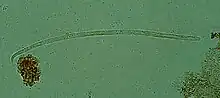

| Onchocerca volvulus, the causative agent of river blindness | |

Onchocerca volvulus is a filarial (arthropod-borne) nematode (roundworm) that causes onchocerciasis (river blindness), and is the second-leading cause of blindness due to infection worldwide after trachoma. It is one of the 20 neglected tropical diseases listed by the World Health Organization, with elimination from certain countries expected by 2025.[2]

Onchocerca volvulus parasites obtain nutrients from the human host by ingesting blood or by diffusion through their cuticle. They may be able to trigger blood-vessel formation because dense vascular networks are often found surrounding the worms.[6] They are distinguished from other human-infecting filarial nematodes by the presence of deep transverse striations.[7]

It is a dioecious species, containing distinct males and females, which form nodules under the skin in humans. Mature female worms permanently reside in these fibrous nodules, while male worms are free to move around the subcutaneous tissue. The males are smaller than females, with male worms measuring 23 mm in length compared to 230–700 mm in females.[7]

The release of oocytes (eggs) in female worms does not depend upon the presence of a male worm, although they may attract male worms using unidentified pheromones.[8] The first larval stage, microfilariae, are 300 μm in length and unsheathed, meaning that when they mature into microfilariae, they exit from the envelope of the egg.[9]